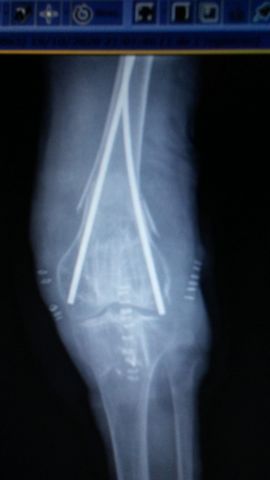

Fractura supracondílea de codo.

Fractura supracondílea de codo.Tras reducción y osteosíntesis.

Fractura supracondílea de codo. Tratamiento con agujas.